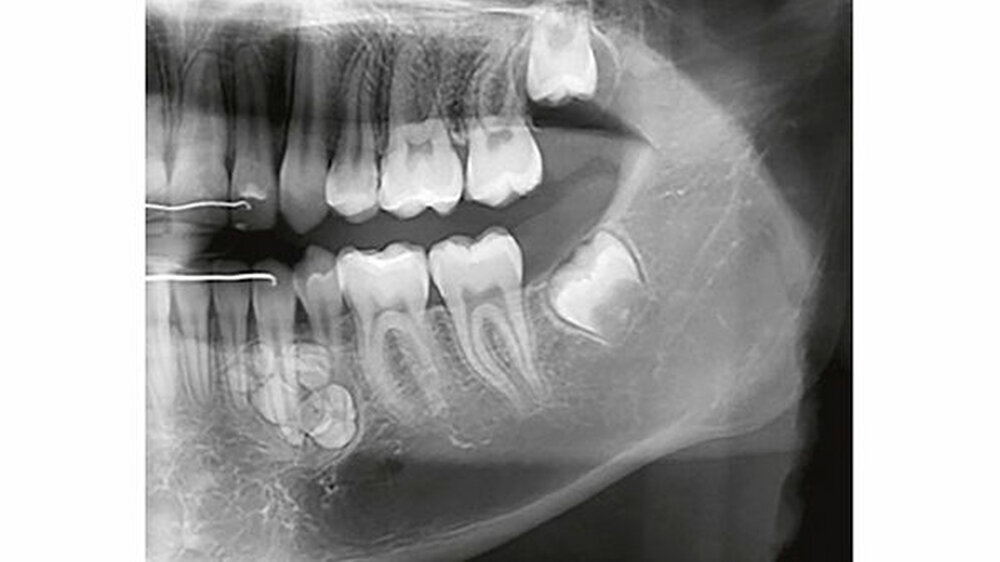

Auf dem mitgelieferten vier Jahre zuvor erstellten Orthopantomogramm (OPT) waren noch keine Hinweise auf das Vorhandensein einer Veränderung regio 32-34 sichtbar (Abbildung 2). Ein Jahr später konnte anhand des OPT bereits eine radioopake Struktur regio 33, 34 festgestellt werden (Abbildung 3). Auf dem aktuellen OPT und digitalen Volumentomogramm (DVT) zeigten sich regio 32-34 lingual multiple, rundliche, unterschiedlich große Radioopazitäten, umgeben von einer radioluzenten Zone.

Die Ränder der radioluzenten Zone waren sehr gut zum umgebenden Alveolarknochen abgrenzbar (Abbildung 4, 5). Eine dreidimensionale Diagnostik (DVT) macht aus dreierlei Gründen Sinn: 1. Erleichterung der Patientenaufklärung, 2. optimale Lagebestimmung des Tumors in Bezug zu benachbarten anatomischen Strukturen wie Nachbarzähne und Nerven, 3. präoperative Bestimmung der Anzahl zahnähnlicher Strukturen (zusammengesetztes Odontom), um kontrollieren zu können, ob während des operativen Eingriffs alle hartgewebigen Tumoranteile entfernt worden sind.